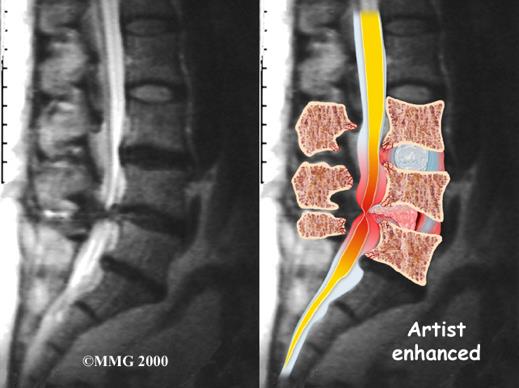

La estenosis espinal lumbar es una enfermedad degenerativa en la que el canal por donde pasan los nervios se vuelve más estrecho.

Este estrechamiento puede comprimir los nervios y provocar dolor, debilidad o dificultad para caminar.

El diagnóstico se confirma principalmente con resonancia magnética, que permite ver el grado de compresión nerviosa y planificar el tratamiento adecuado.